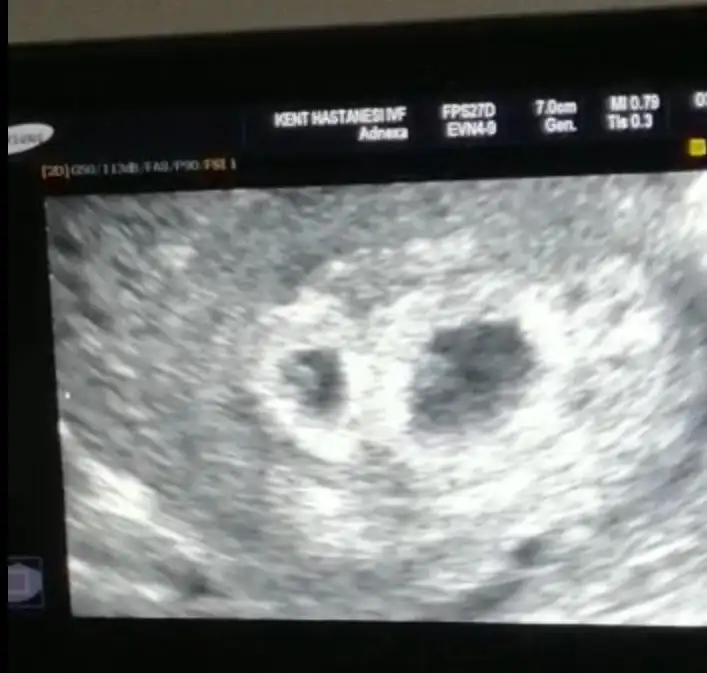

Kız bence ikiside ama ikra meyrada baksın yinedemerhaba anneler, benim bebelerim için de tahminde bulunurmusunuz. 6 haftalık vajinal ultrasyon

Evet iyi olur emin olalim en azındanPazartesi 13 haftalık olacağım o zaman tekrar atayım başka doktora gideceğim onun tahminini de yazarım. İnşallah kızdırAslında ikiz hamileydim çift yumurta biri kız birisi erkek oluyorlar genellikle. Kesemin birinde plesanta oluştu bebek gelişmedi. Hangisi daha güçlüydü o yönden de merak var hala aynı boyda iki kesem var çok üzücü.